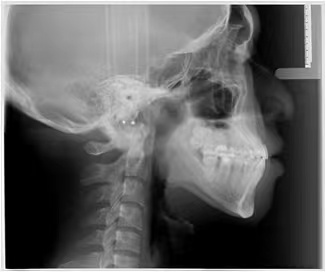

情况:不接受外科手术,在当地做了1年半的矫治,遇到困难无法进行。由外地正畸同行推荐来上海寻求非手术矫治的二手病例。武广增老师接收时的错合畸形情况,呈现严重的骨性反合偏合及侧方开合(图1-图10)。由于推荐其去口腔医院接受正颌外科手术遭到拒绝,武广增老师通过专业的检查、分析,制定一套详细的治疗计划,采用了磨牙推进器技术、武式辅弓技术等特色正畸手段获得明显效果(图2-1~图2-9)。治疗结束后也拍摄了相关照片(图3-1~图3-9)。

矫治前

图10